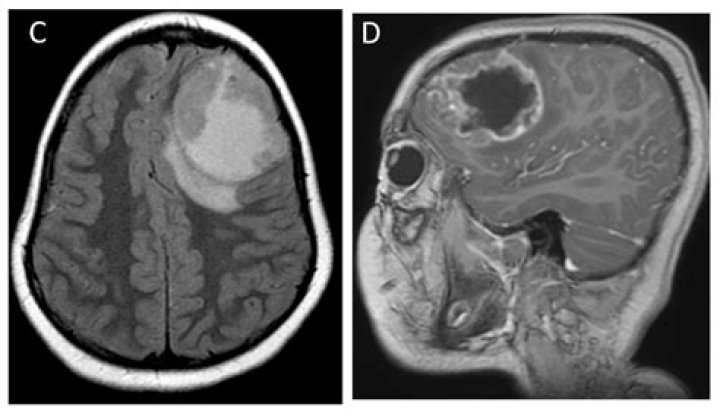

Cystic AA can be easily misdiagnosed as neurocysticercosis merely based on clinical symptoms, MRI and the immunological testing due to the similarity of the glioma and cysticercus antigens. Pathological investigations following surgical treatment are vital for the management of this condition.